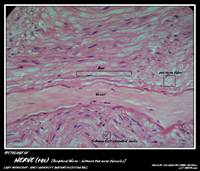

NERVE TISSUE